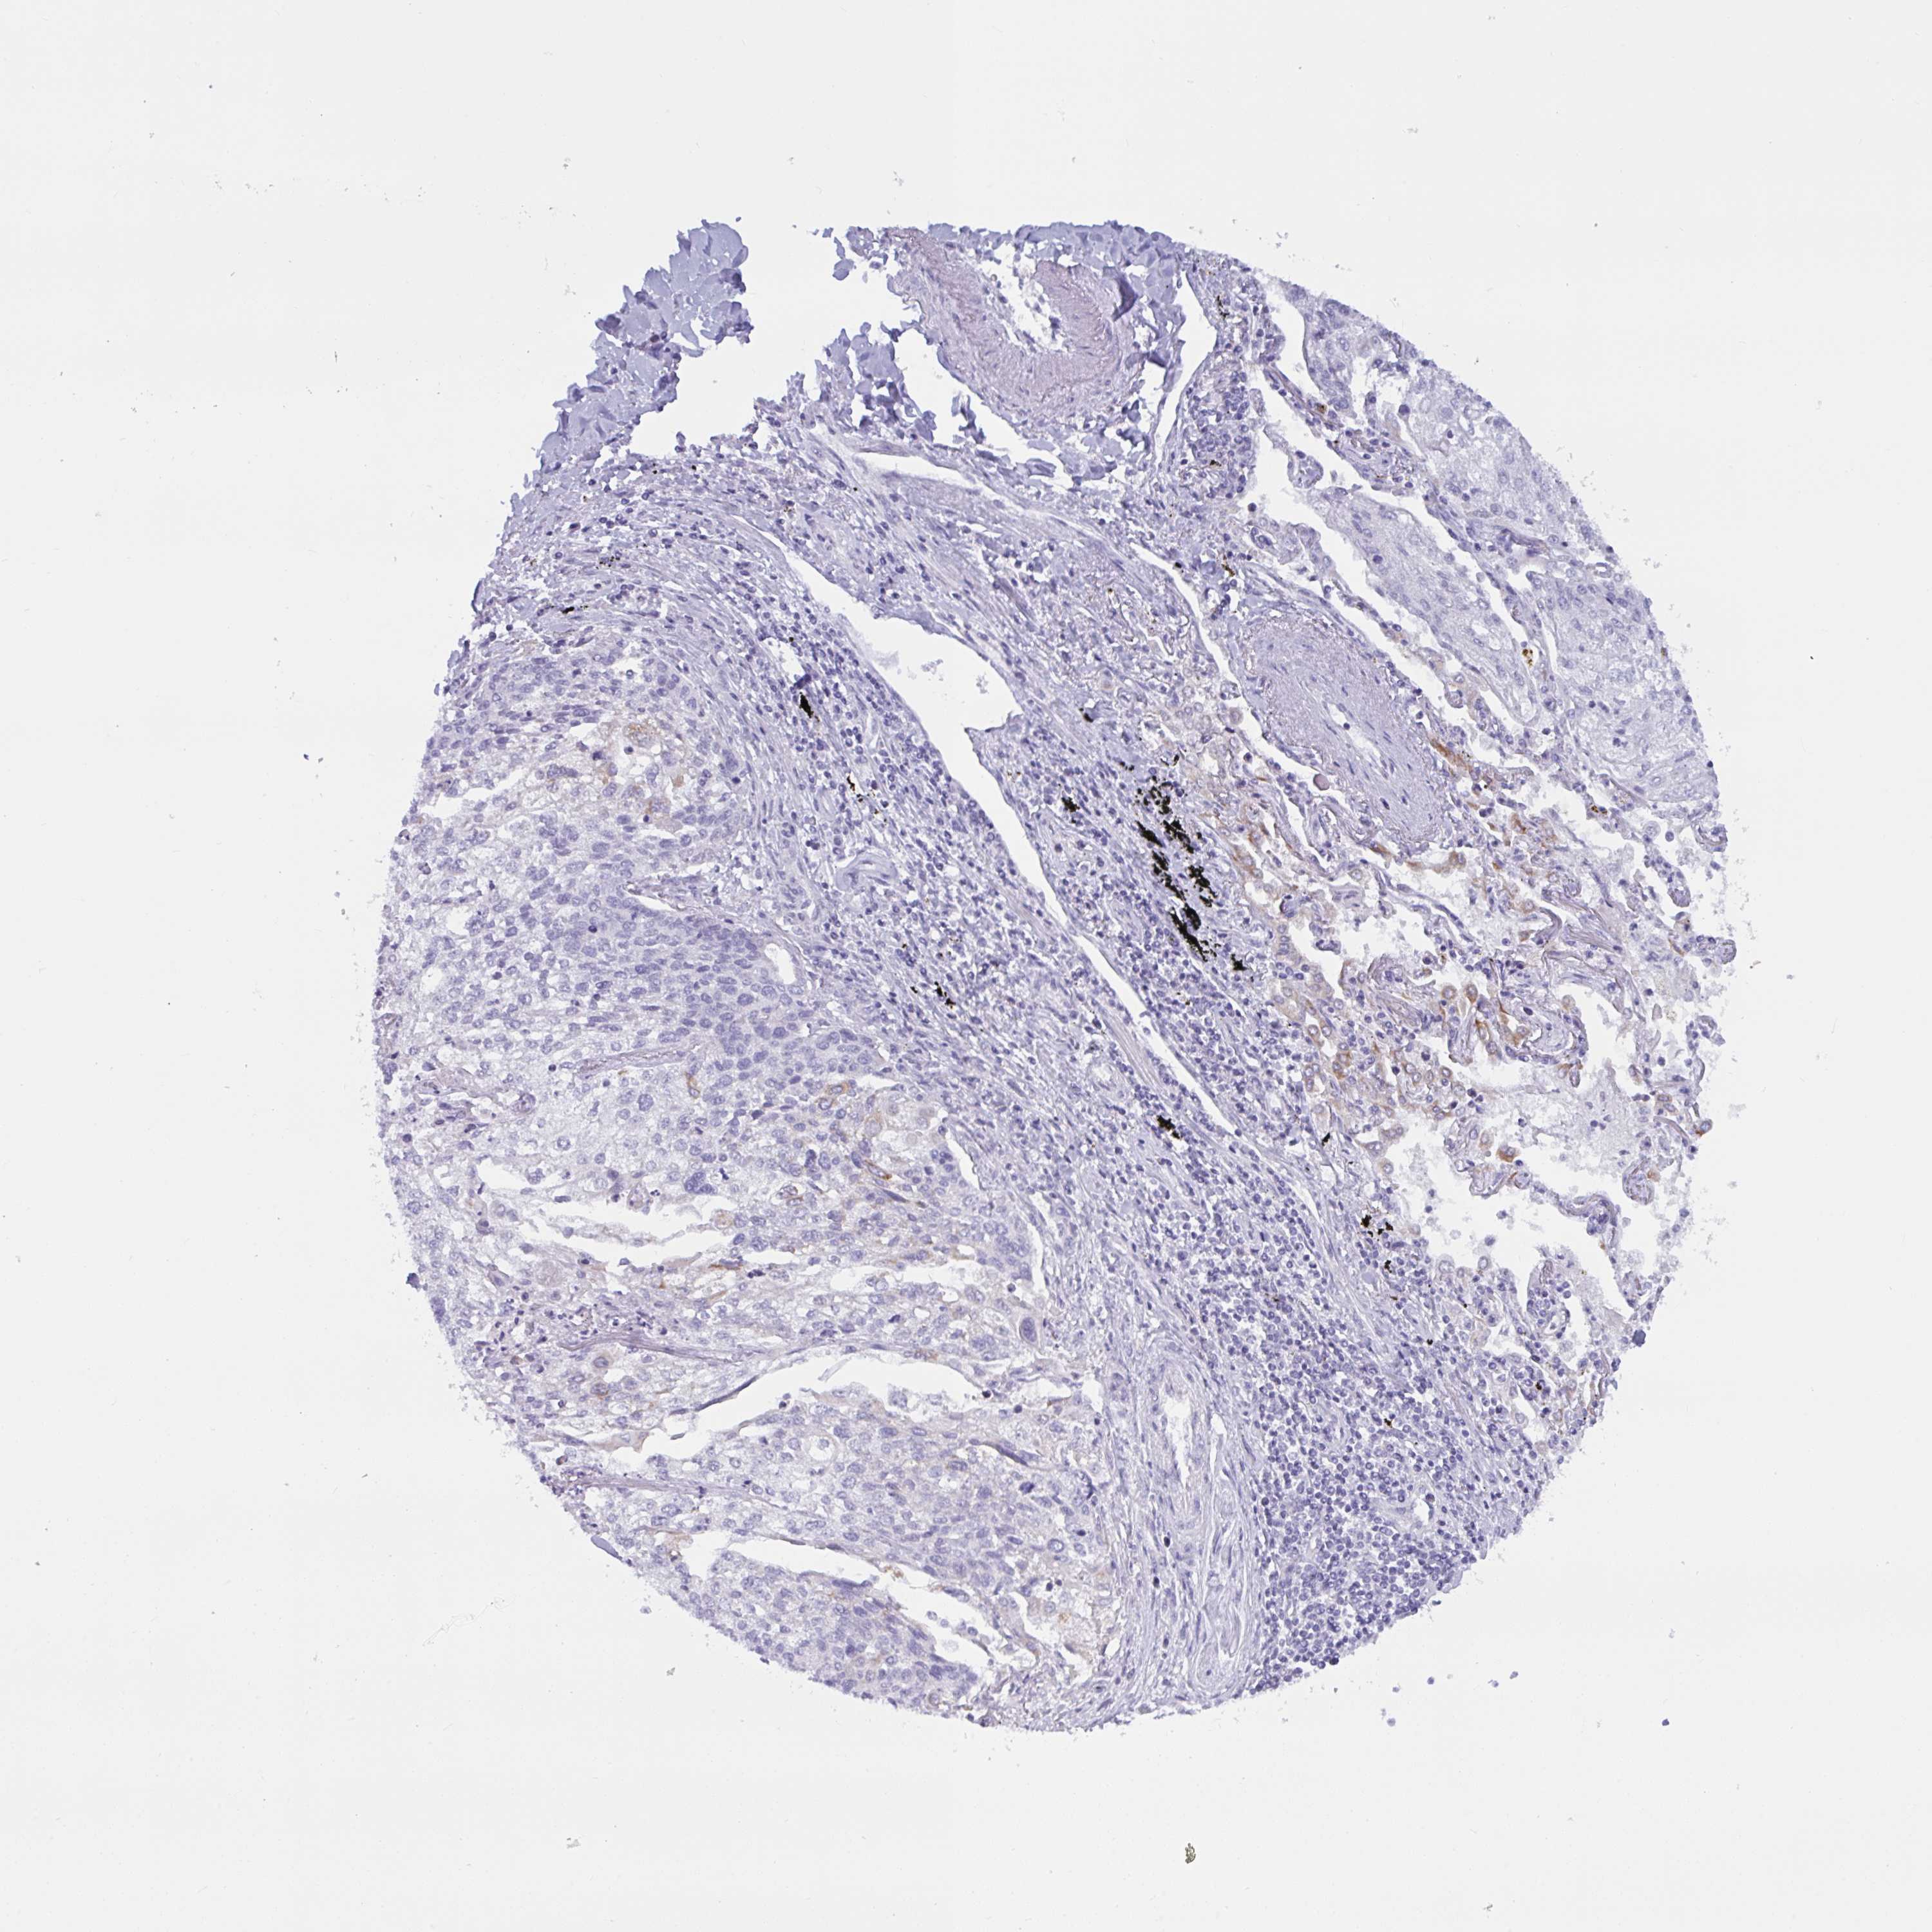

CANCER LUNG CANCER Show tissue menu

Lung cancer

Human cancer

Lung adenocarcinoma

TANK is not prognostic in Lung Adenocarcinoma (TCGA)

Average pTPM 41.8

Number of samples 497